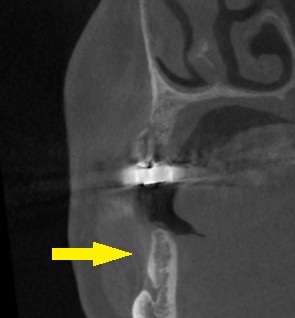

ご了承いただけましたので、本日、2本のインプラント埋入と、骨造成術を行いました。

下の写真3段目が手術後のCTです。